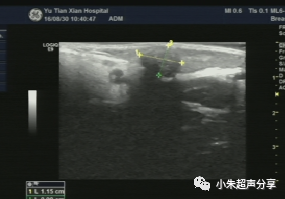

病例2 女 ,5岁,项部毛母质瘤,

其内未见血流信号